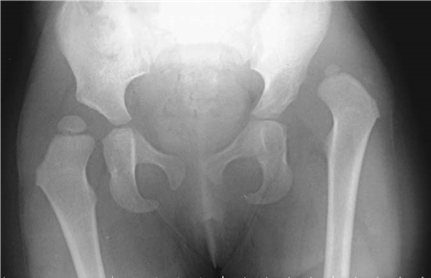

The epidemiology of Dupuytren’s contracture is heavily skewed toward individuals of Northern European descent, earning it the historical moniker of the "Viking disease." It exhibits an autosomal dominant pattern of inheritance with variable penetrance. The concept of "Dupuytren’s diathesis" is critical for the clinician to understand, as it denotes a highly aggressive, recurrent form of the disease. Patients with the diathesis typically present at an earlier age, have a strong family history, exhibit bilateral involvement, and frequently present with ectopic fibroproliferative manifestations such as Ledderhose disease (plantar fibromatosis), Peyronie’s disease (penile fibromatosis), and Garrod’s pads (dorsal knuckle pads). Identifying these patients preoperatively is paramount, as their recurrence rates following surgical intervention are markedly elevated, often necessitating more radical surgical approaches such as dermofasciectomy.

A multitude of environmental and systemic risk factors have been conclusively linked to the onset and progression of the disease. These include chronic liver disease, excessive alcohol consumption, smoking (which induces microvascular ischemia), diabetes mellitus, and epilepsy (particularly associated with the long-term use of certain antiepileptic medications like phenytoin). Furthermore, occupational hazards involving repetitive manual labor or the use of vibratory tools have been implicated in exacerbating the micro-trauma cascade that triggers fascial proliferation. In the pediatric population, while true Dupuytren's is exceedingly rare, the surgeon must maintain a high index of suspicion for other fibromatoses or congenital contractures that mimic this presentation, ensuring that genetic and syndromic workups are initiated when appropriate.